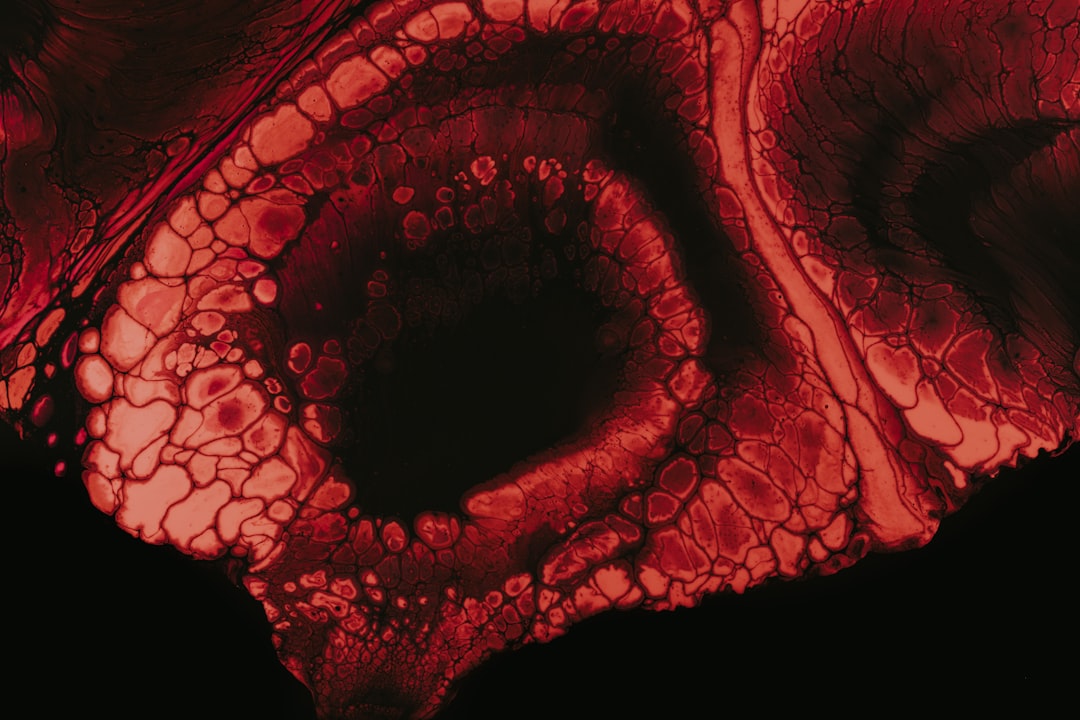

대장암 의심 증상으로는 다른 증상들도 다양하게 존재합니다. 이러한 증상들은 보통 대장 내에서의 이상 소견을 바탕으로 합니다. 간혹 대변에 혈액이나 점액이 섞여 나오는 경우가 있는데, 이것은 결코 가벼운 증상이 아닙니다. 실제로 제 주변에서 이러한 증상을 겪었던 지인이 있었는데, 초기 검사로 인해 조기에 대장암이 발견되었습니다. 모두가 이처럼 본인에게 소중한 시간을 소홀히 하지 않도록 하길 바랍니다.

또한 변의 형태가 수시로 달라지는 느낌이나, 배변 후에도 불편함이 느껴지는 ‘불완전 변배출 증후군’도 주의해야 할 증상 중 하나입니다. 이는 대장 기능에 문제가 생겼음을 나타낼 수 있습니다. 이런 다양한 증상들 중 어느 하나라도 느껴진다면, 절대 가볍게 지나치지 마세요. 각자의 몸이 주는 신호를 듣는 것은 정말 중요한 일이니까요.